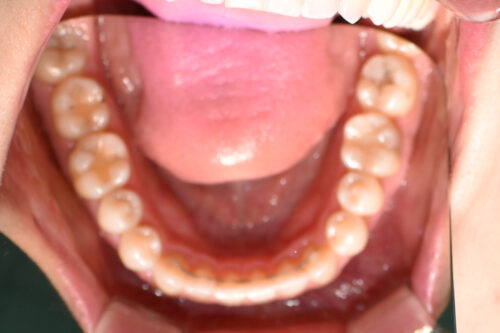

開咬(前歯が噛まない、隙間がある)かみ合わせ変化ワイヤー9か月

初診時年齢28歳女性

歯のがたつき(叢生)と

出っ歯

と

開咬

を気になさり

巣鴨 ・ 池袋よりひとつ隣駅の東京都豊島区大塚駅すぐの大塚たまみ矯正歯科へ

来院されました。

ワイヤー矯正治療9か月後です。